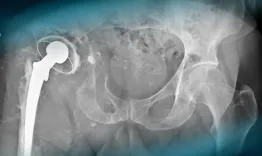

A 57-year-old man with a history of hypertension and a right hip replacement in 1993 presents with worsening right hip pain over 10 years. He uses one cane, has a 3 cm leg length discrepancy, and a soft mass in the groin. What are your diagnostic hypotheses?

Complex hip revision in a patient with massive massive loss bone stock